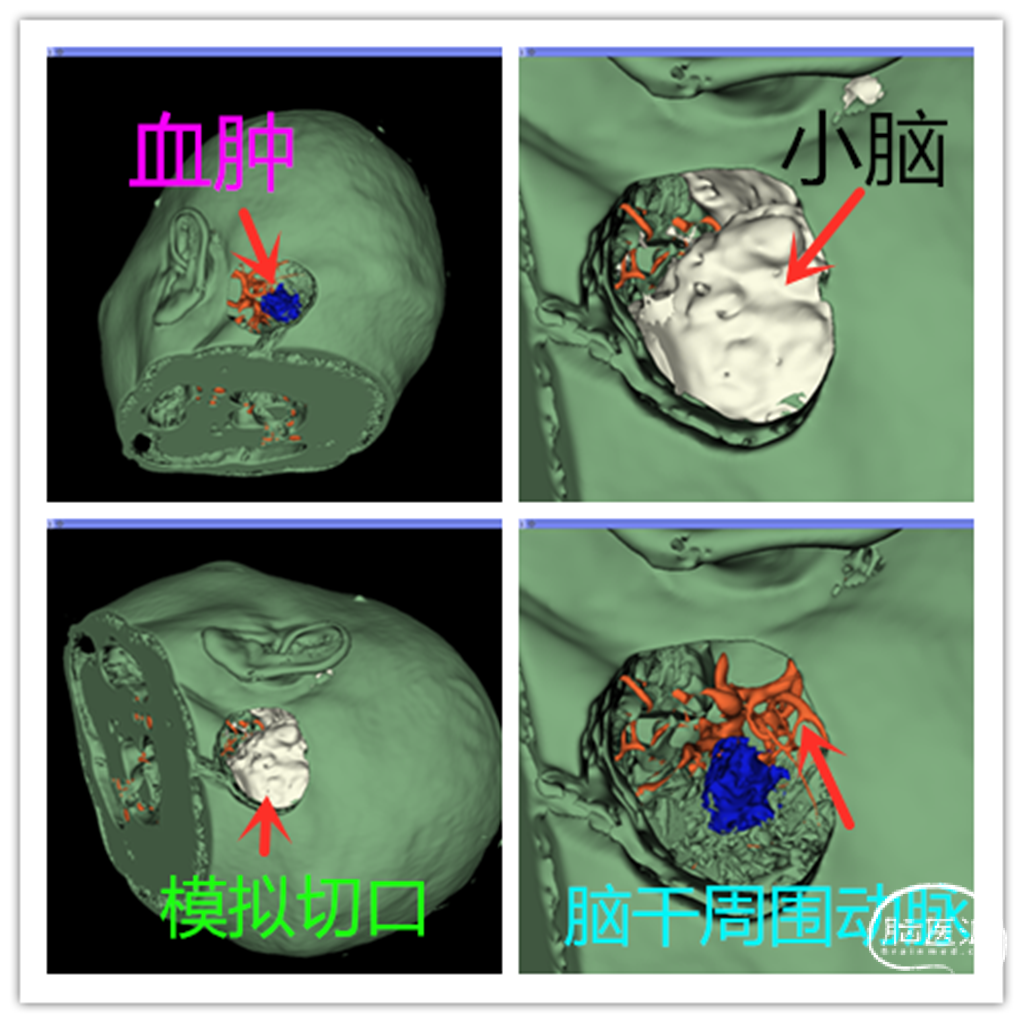

图 2 CTA及手术模拟

患者病情危重,呼吸节律紊乱,建议药物治疗,观察。患者家属充分了解病情,坚决要求手术治疗,反复告知后仍坚持手术。拟行经左侧乙状窦后入路脑干血肿清除术。